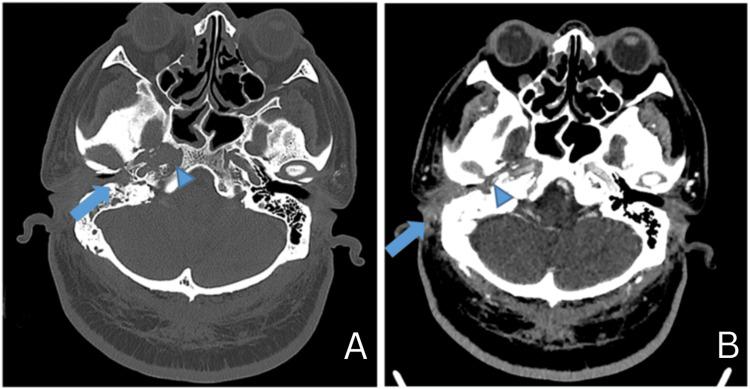

Abstract

Skull base osteomyelitis is a not commonly encountered but potentially fatal consequence of untreated necrotizing otitis externa. Early recognition and appropriate treatment are crucial to prevent serious complications such as cranial nerve palsies, meningitis, and intracranial abscess formation. The case reports presented in this study provide a rich depiction of the clinical presentation, diagnostic challenges, and interventions employed. Early recognition and appropriate management of skull base osteomyelitis are crucial to prevent complications and improve patient outcomes.